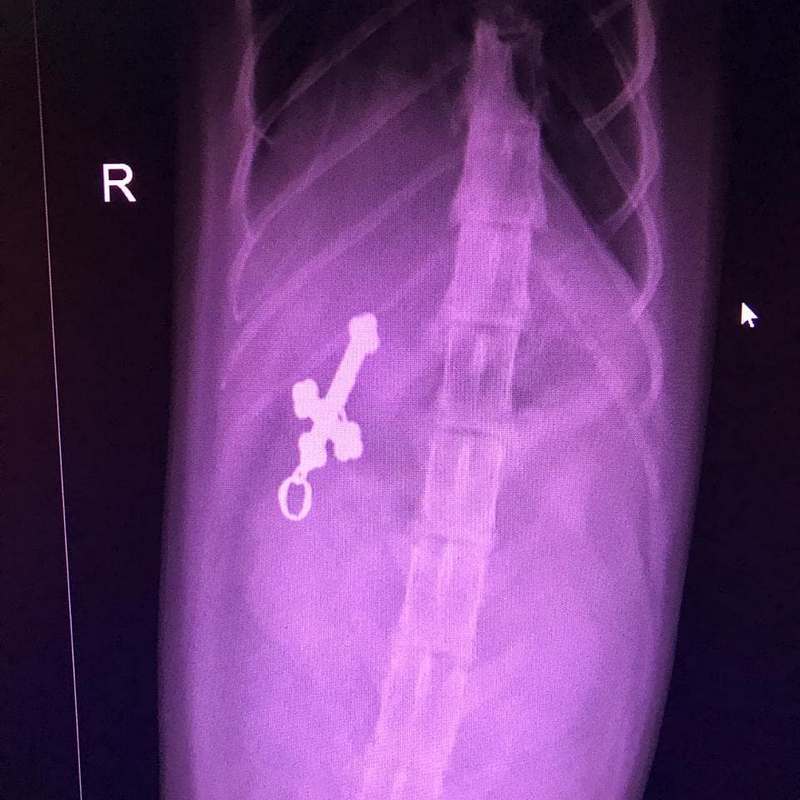

«Когда ему сделали рентгеновский снимок, на экране монитора наши специалисты увидели нательный крестик, который оказался в желудке у кота! Нашему изумлению и удивлению владельцев не было предела! В какое время котик его съел и, самое главное, как — никто не знает», — сообщили специалисты в посте.

В Кузбассе ветеринары спасли кота, который проглотил нательный крестик. Необычный случай произошёл вечером 6 января в одной из новокузнецких ветеринарных клиник. Об этом сотрудники ветклиники @vetsovet42 сообщили в соцсетях.

Отмечается, что после оперативного вмешательства крестик вернули хозяевам животного, а сам пациент ветклиники пришёл в себя в стационаре.